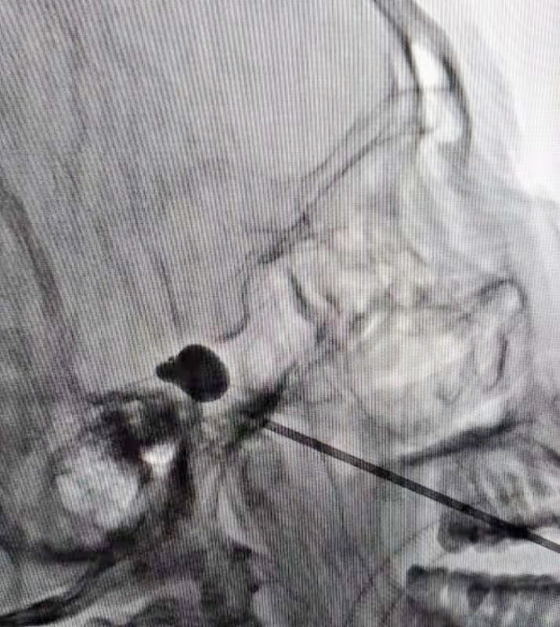

该手术在医用X线透视设备的引导下,将一个微球囊刺入三叉神经的半月节,然后缓慢注入对比造影剂充盈球囊,解除导致三叉神经痛的神经纤维卡压症状、并通过扩张的微球囊产生压迫破坏作用,从而对三叉神经进行治疗。此项手术属于近年来三叉神经痛治疗的新进展,为我院首例,填补了科室在此领域的空白,既丰富了我院麻醉科疼痛病房对三叉神经痛的治疗方法,也为药物治疗效果不明显的原发性三叉神经痛患者带来了福音。

因患者高龄,长期患冠心病、慢性支气管炎、高血压病,同时左肾因结石导致萎缩,本人及家属拒绝行开颅手术治疗。经湘雅医院麻醉科程智刚教授、白念岳副教授及我院麻醉科孙志华主任联合会诊后决定行左侧三叉神经半月节微球囊压迫术,此手术创伤小、风险低、恢复快、患者耐受性好。经过充分沟通,患者及家属欣然接受。术前准备就绪后,于12月3日在全麻下行“左侧三叉神经半月节微球囊压迫术”治疗。术后患者疼痛完全消失,手术获得圆满成功。